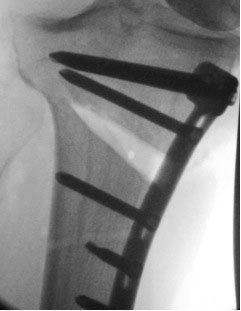

This is an 'opening-wedge' osteotomy, where the surgeon has cut into the bone and prised it into a better alignment, which is then fixed with a plate and screws until the bone is healed in the new position.

Illustration of the plate and screws holding the wedge open.